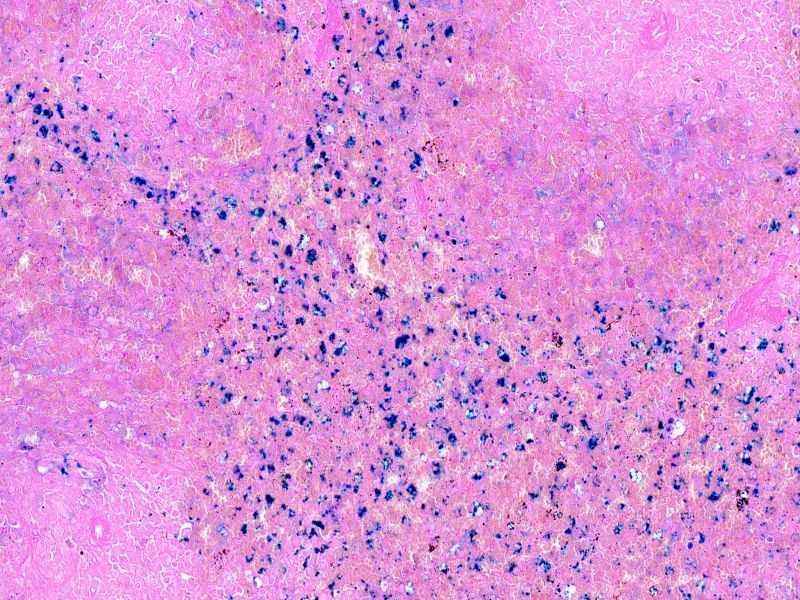

普鲁士蓝染色

编号:YSY10122